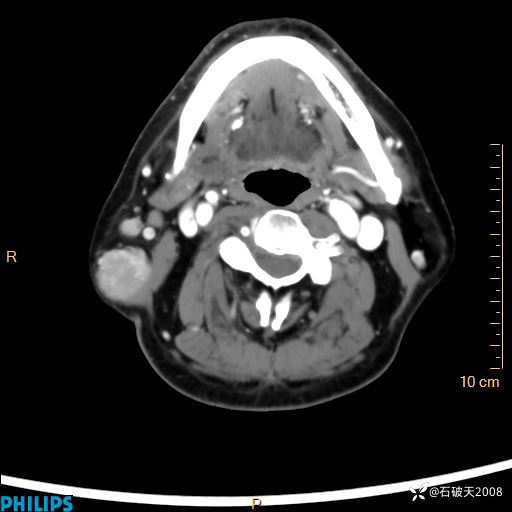

病例分享:颈部占位,一周后公布病理

男 57岁 主 诉:发现右侧颌下肿物1月余。

现病史:1月余前家属发现右侧颌下肿物。局部皮肤无红肿、热痛,无吞咽困难,无异物感,无恶心、呕吐,无头痛、头晕,无胸闷、胸痛,无发热、咳嗽、咳痰及呼吸困难。于我院行体表肿块彩超检查(2024.03.15我院)示:右侧耳下皮下软组织内低回声,未治疗。今为进一步治疗门诊以“腮腺肿瘤”为诊断收住我科,发病来患者神志清,精神可,饮食、睡眠及大小便正常,体重无明显下降。

平扫